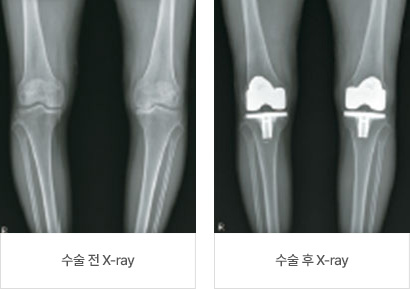

인공 슬관절 치환술

인공 슬관절 치환술’이란 퇴행성 관절염 또는 다른 원인 질환에 의해 닳아 망가진 관절면을 특수 금속과 고강도 플라스틱을 이용하여 관절면을 바꾸는 수술입니다. 일반적으로 무릎 관절의 파괴가 심하게 진행되고 보존적 치료를 시행하였음에도 불구하고 통증이 가라앉지 않는 경우에 인공 슬관절 치환술을 시행하게 됩니다. 이 수술은 무릎 관절염으로 인한 동통을 완화시켜 주며 좀 더 활동적인 삶을 유지하도록 하는 수술입니다.